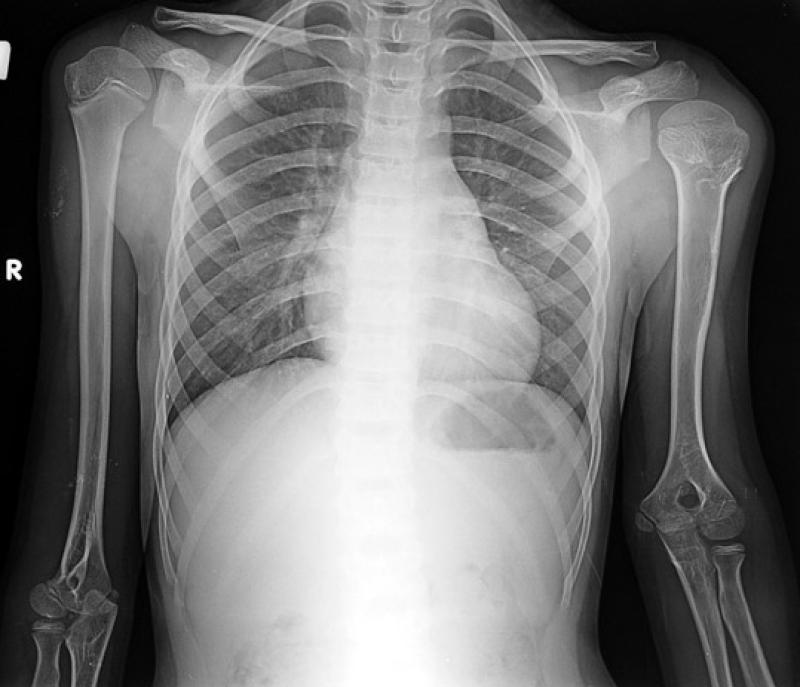

For lengthening surgery, the individual needs to be diagnosed with short stature first. To diagnose short stature, after examining patient history, physical examination and laboratory evaluations are made. In the physical examination stage, the length of arms and legs of patients between fixed points is measured and both standing and lying calculations are made. Also, special stature roentgens are used for millimetric measurements.

In the laboratory measurements; patient’s bone age, blood count for chronic disease analysis, full urinalysis, liver function measuring, stool test, PH ratio in blood, lung graphy, erythrocyte sedimentation rate, ure, sodium, potassium, calcium, phosphor, thyroid hormones, albumin, chromosome, and antibodies can be analysed.